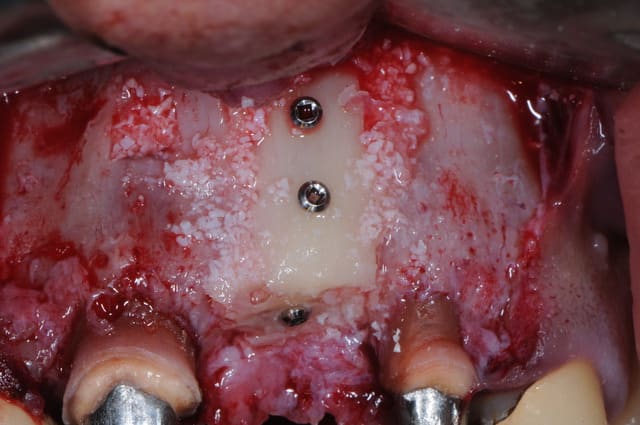

la photo de la pose de l'implant faite par un confrère sur le dernier cas

j'ai toujours une grade frustration à ne pas voir directement le résulta de la greffe quand je ne fais que cette dernière et que les correspondants posent eux même l'implant

temps "greffe" et temps "pose implant"